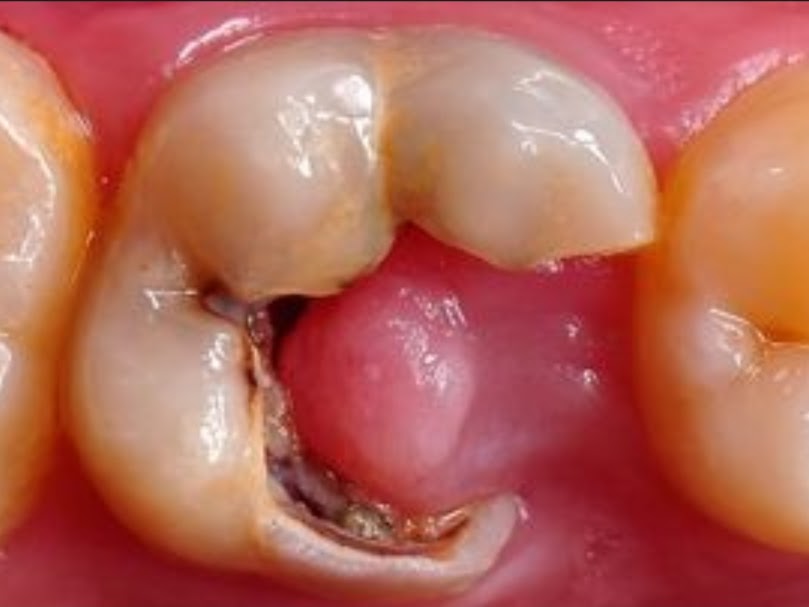

Polip pulpa atau pulpitis hiperplastik adalah pembengkakan jaringan pulpa pada gigi berlubang sebagai reaksi terhadap iritasi akibat pembusukan gigi.

Namun, kondisi ini menyebabkan hal sebaliknya karena iritasi malah membuat jaringan pulpa terus tumbuh.